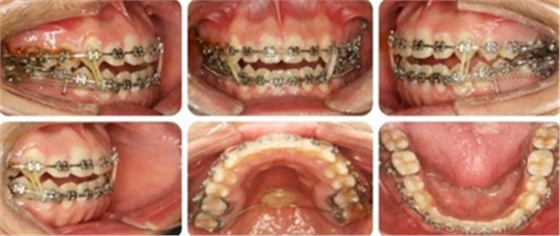

治療過程

6個月,上牙列擁擠得到解除。上下頜植入種植釘,用于上后牙壓低及下牙列遠(yuǎn)移。

14個月,前牙開頜得到改善,配合使用垂直牽引。